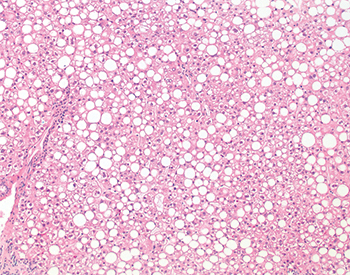

Hepatic steatosis is assessed as the percentage of the biopsy involved by macrovesicular or “large-droplet” steatosis. In macrovesicular steatosis, one or a few large fat droplets displace the nucleus to the edge of the hepatocyte (Fig. 3.1.4). Frozen section may be used to assess potential graft organs for steatosis because steatosis cannot be reliably assessed by gross evaluation, and moderate or severe steatosis has been associated with increased risk of poor or delayed graft function in some series. There is no uniformly acceptable amount of steatosis, and reported graft and patient outcomes for steatotic livers vary widely. Grafts with less than 30% steatosis are usually considered suitable for transplantation (Fig. 3.1.5), whereas those with greater than 30% (Fig. 3.1.6) or even greater than 60% (Fig. 3.1.7) are less desirable but have been used successfully in some circumstances. Special stains for fat (oil red O) may be used in steatosis assessment but are not required. “Small-droplet” steatosis refers to a single or few small lipid droplets that do not displace the nucleus (Fig. 3.1.8). This finding alone does not adversely impact graft function. Pure microvesicular steatosis is a rare finding that manifests as multiple tiny lipid droplets that surround the nucleus and impart a foamy or vesicular appearance to the hepatocyte cytoplasm (Fig. 3.1.9). Pure microvesicular steatosis likely represents an agonal or ischemic change that does not impact graft function.